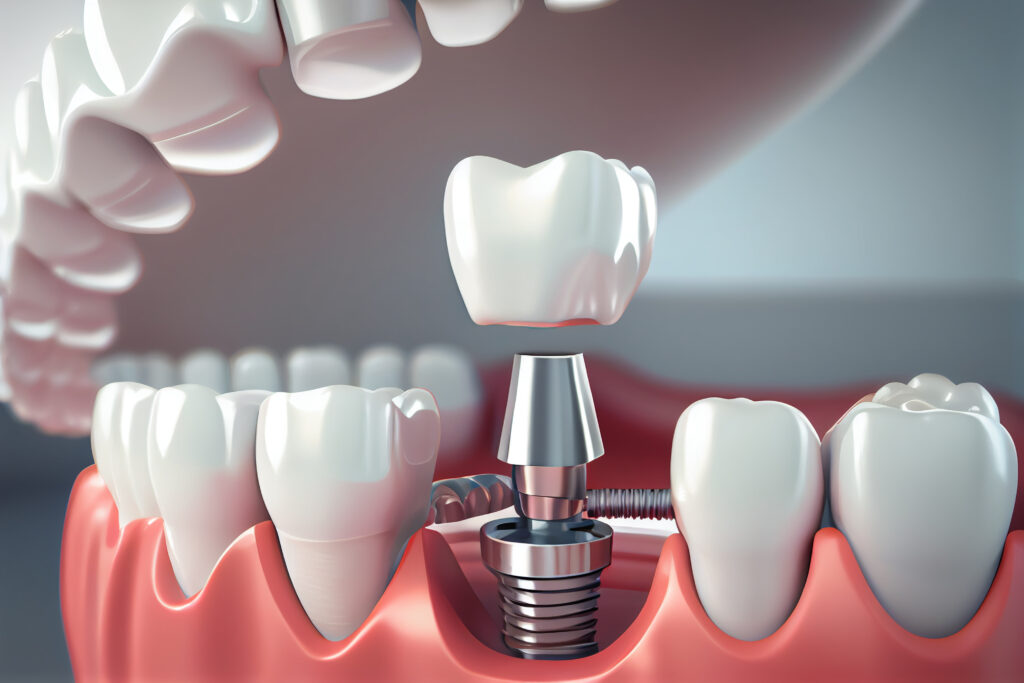

Cấy ghép Implant là phương pháp phục hình răng mất hiệu quả nhất hiện nay, giúp khôi phục thẩm mỹ và khả năng ăn nhai bình thường. Bài viết dưới đây sẽ trình bày chi tiết về cấy ghép Implant, ưu điểm của phương pháp này, và khi nào nên hoặc không nên thực hiện. Cấy ghép implant là gì? Cấy ghép Implant, hay trồng răng Implant, là quá trình sử dụng một trụ chân răng nhân tạo bằng Titanium được đặt vào xương hàm tại vị trí răng đã mất. Trụ chân này thay thế chân răng thật, sau đó được gắn với răng sứ, tạo thành một răng hoàn chỉnh. Cấy ghép implant là phương pháp nha khoa tiên tiến sử dụng để phục hồi răng đã mất một cách tự nhiên và lâu dài. = Cấy ghép implant là gì? Ưu điểm của cấy ghép implant Cấy ghép implant là phương pháp nha khoa hiện đại được sử dụng để phục hình răng đã mất một cách hiệu quả và lâu dài. So với các phương pháp truyền thống như hàm giả tháo lắp hay cầu răng sứ, cấy ghép implant mang lại nhiều ưu điểm vượt trội, bao gồm: Chức năng ăn nhai tối ưu Implant được cấy trực tiếp vào xương hàm, đóng vai trò như chân răng thật, giúp bạn có thể ăn nhai thoải mái như răng thật mà không lo bị xô lệch hay khó chịu. Khôi phục khả năng nhai 90-95% so với răng thật, giúp bạn tự tin thưởng thức mọi món ăn yêu thích. Thẩm mỹ cao Implant có màu sắc và hình dạng giống như răng thật, giúp bạn sở hữu nụ cười tự nhiên và rạng rỡ. Ngăn ngừa tình trạng tiêu xương hàm, giúp duy trì